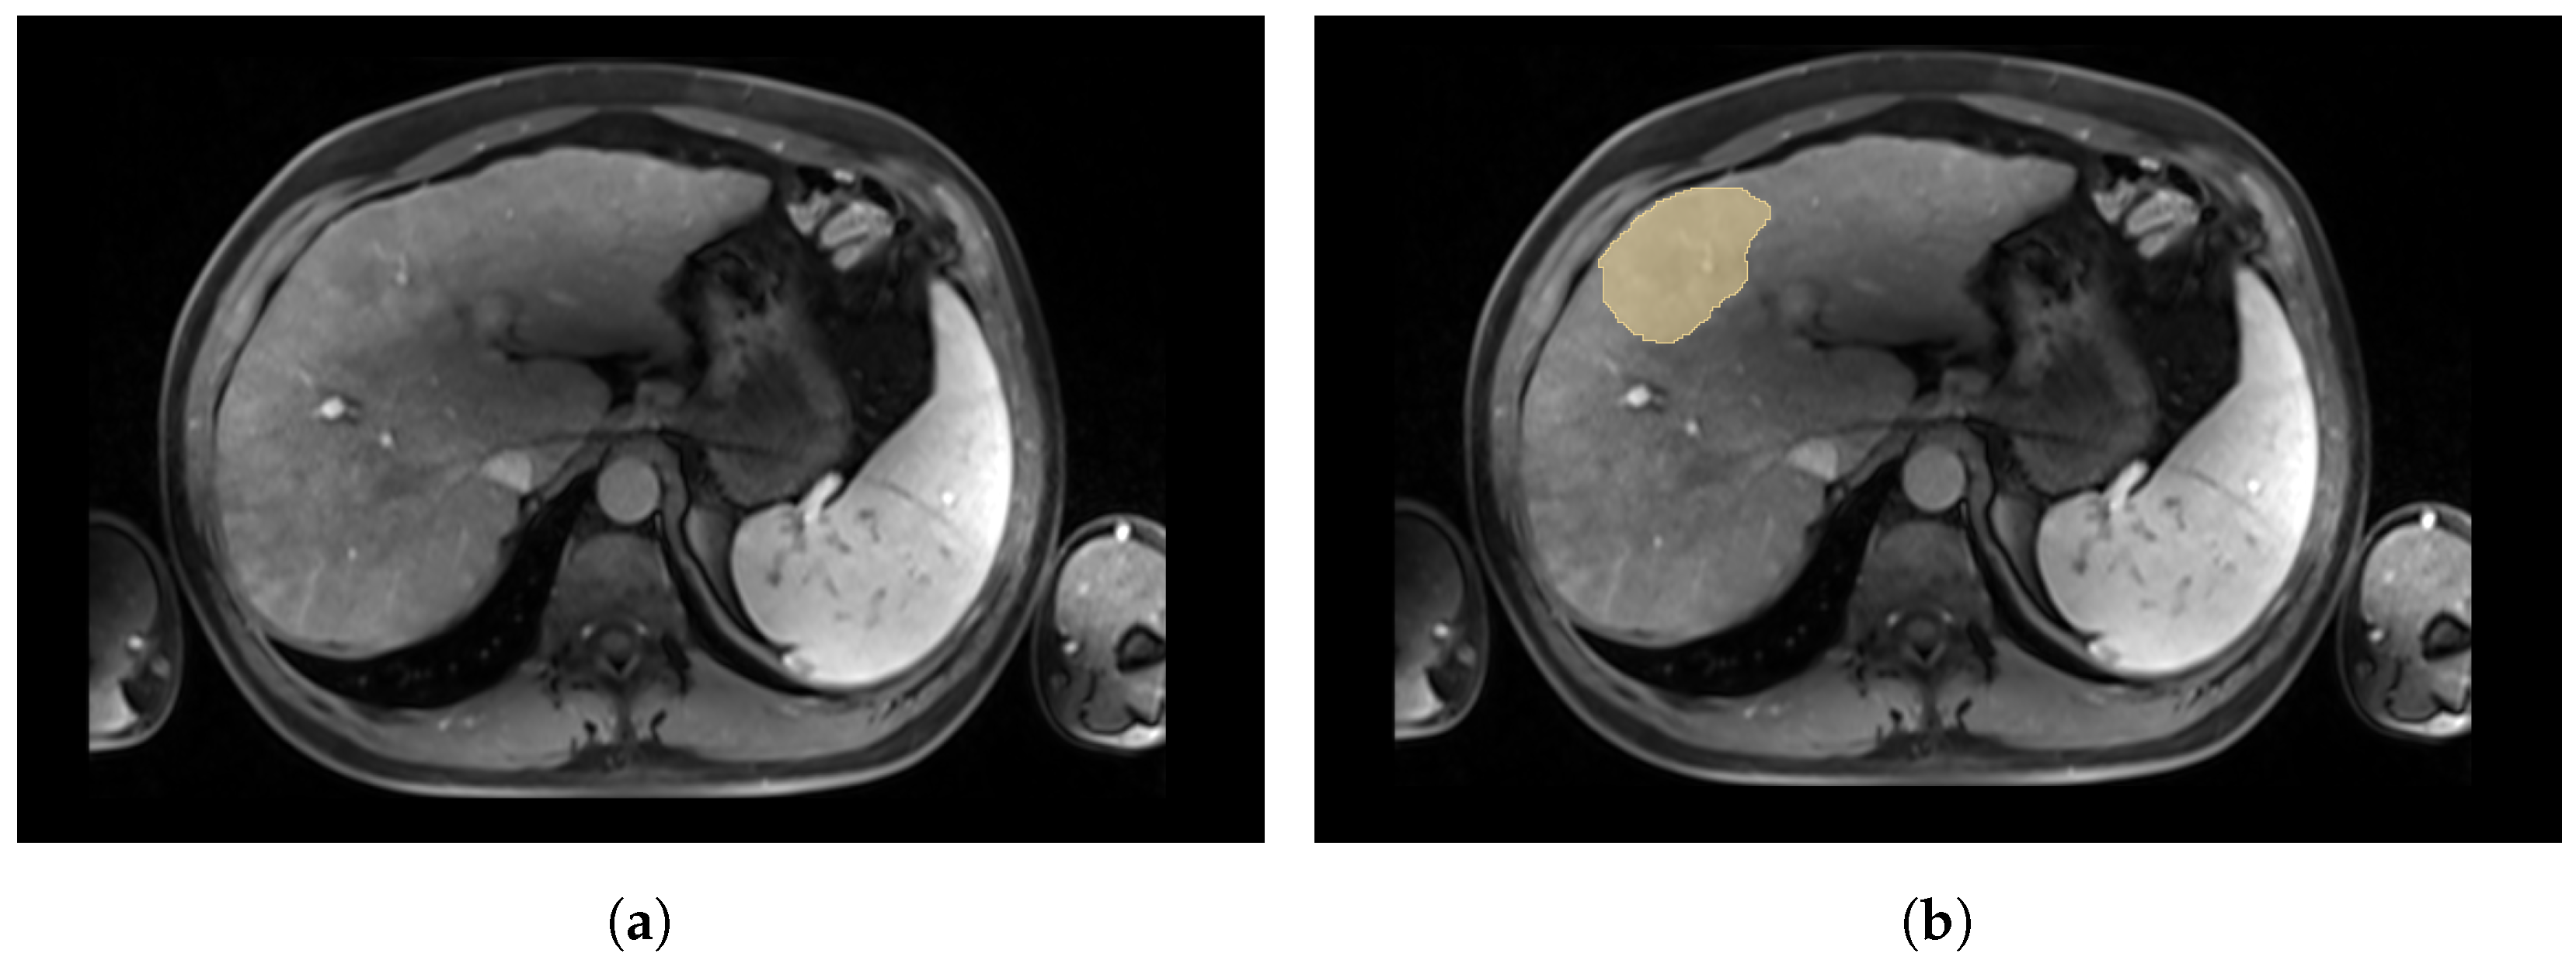

Since the dataset is composed of real clinical cases, the acquisition conditions may vary. Although enhancement of the tumour is expected after injection of the contrast agent, in practice, some cases, such as in Figure 4, still present a low contrast between the tumour and the liver. This situation complicates greatly the manual segmentation by the radiologist and thus the quality of the labels.

Figure 4.

Axial slices of a CE-MRI from a patient with low contrast between tumour and liver. (a) Axial slice of a CE-MRI from patient with low-contrast tumour. (b) Axial slice of a CE-MRI from patient with tumour label. A very low contrast between the liver and the tumour in yellow was observed in the arterial phase for this patient.